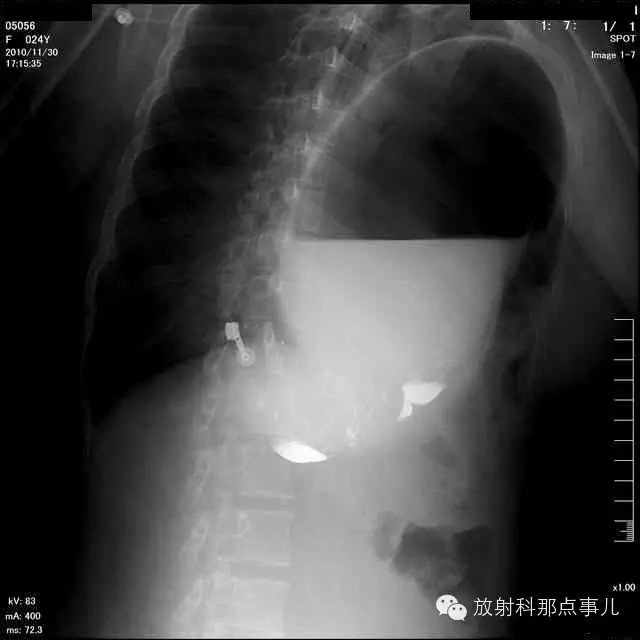

门诊腹部透视发现左侧胸腔巨大气液平面,为排除膈疝口服钡剂,但造影剂未见进入胃内。嘱住院,外科给予胃肠减压、补液等处理常规处理(未引流出明显气、液体)。5个半小时后再次检查,见少量造影剂进入消化道;为进一步了解情况,予泛影葡胺分别经胃管推注及口服,但均未进入胃内。当天进行外科急诊手术。

更正:检查时间在左上方。

大部分胃、脾及横结肠均经过胸肋三角疝入左侧胸腔内,并见疝环形成。

考虑该患者因生产过程中腹压急剧升高,导致腹内脏器经膈肌缺损或薄弱部位进入胸腔内。